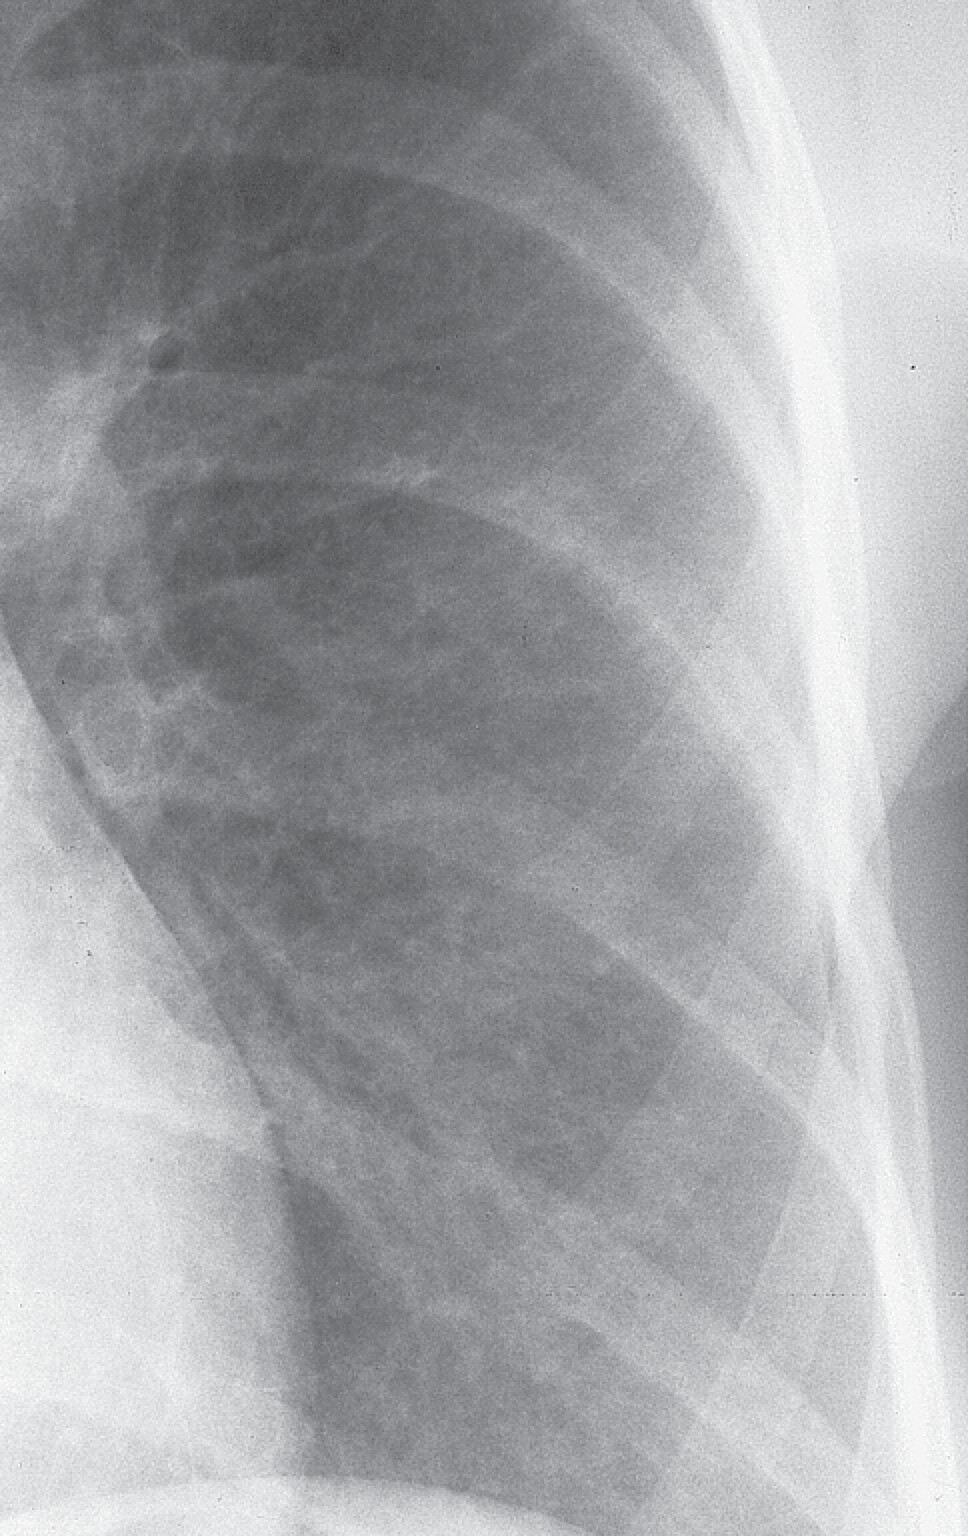

In der Lungenfunktionsanalyse zeigt sich eine restriktive Ventilationsstörung mit kleiner TLC (totale Lungenkapazität) und Behinderung des CO-Transfers (Diffusionsstörung). In Ruhe kann die Blutgasanalyse normal ausfallen, unter leichter Belastung (40 Watt) jedoch entwickelt sich eine Hypoxämie. Das HR-CT kann bereits frühe Stadien der EAA nachweisen (disseminierte Milchglastrübungen, Retikulationen, Fibrose), die in der Röntgen-Thorax-Übersicht oft schwer zu erkennen sind. In der Röntgen-Thorax-Übersicht in 2 Ebenen findet sich eine disseminierte, feinfleckige, manchmal feinretikuläre Zeichnungsvermehrung über allen Lungenabschnitten (Abb. 27.5). Für die Diagnostik ist das HR-CT, wie bei allen interstitiellen Lungenerkrankungen essenziell. Die akute EAA zeigt dabei ein relativ typisches Muster mit großflächigem Milchglas und häufig ein sogenanntes Mosaikmuster. Die chronische EAA zeigt dagegen unterschiedliche radiologische Muster, sodass die Diagnose sich oft schwierig gestaltet.

Abb. 27.5 Röntgen-Thorax-Übersicht bei exogen-allergischer Alveolitis

Disseminierte kleinfleckig-retikuläre Lungenzeichnung.

a Übersichtsaufnahme.

b Detailaufnahme linkes Unter- und Mittelfeld.